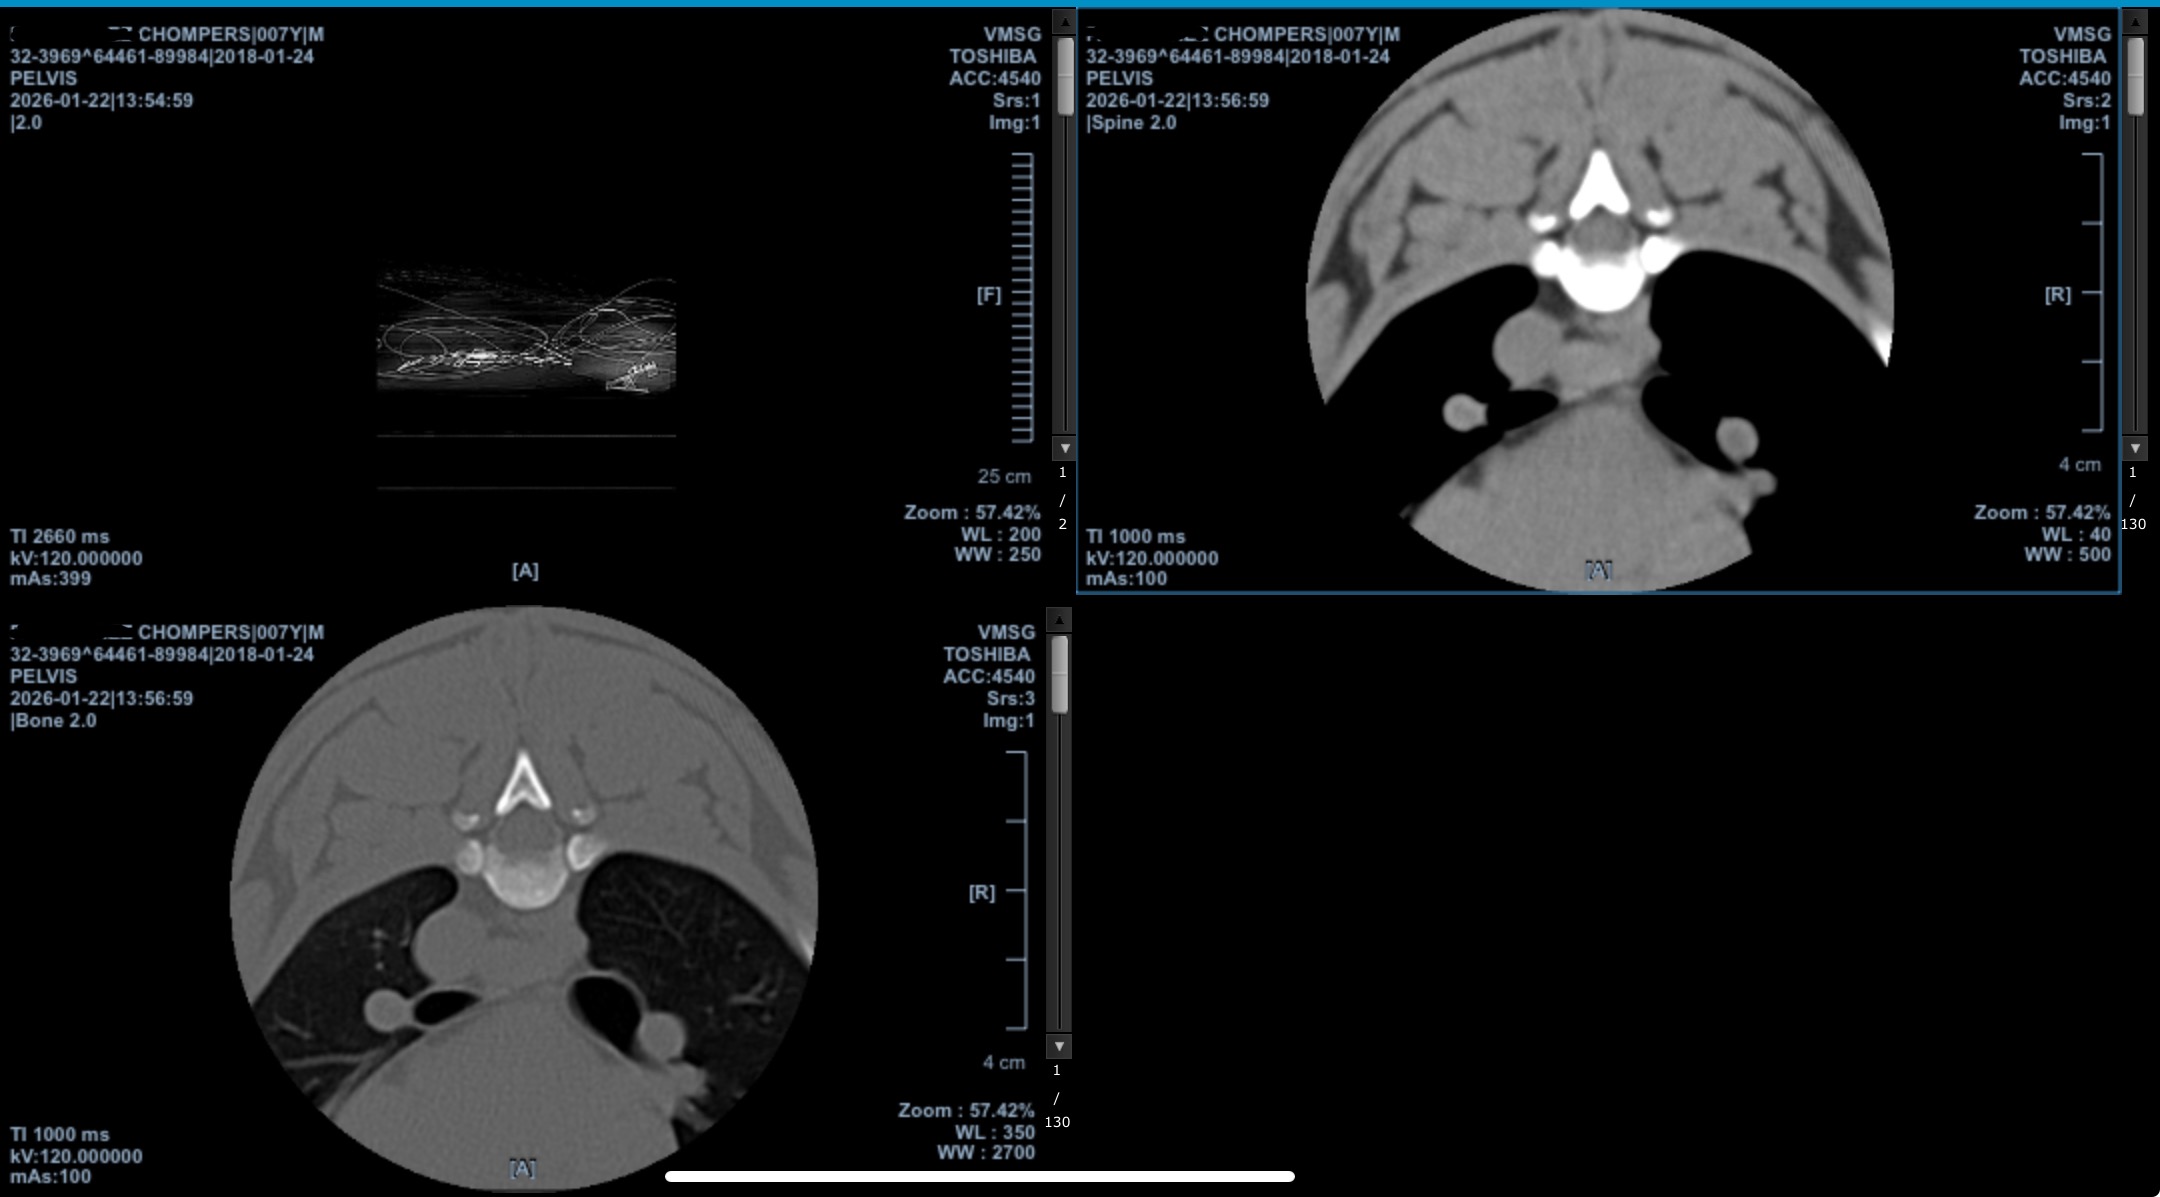

After multiple emergency veterinary visits, lab work, radiographs, CT imaging, and a neurology consultation at Veterinary Medical & Surgical Group (VMSG), Chompers was diagnosed with severe intervertebral disc disease (IVDD) with a confirmed herniated disc compressing his spinal cord.

The neurologist has strongly recommended urgent decompressive spinal surgery (hemilaminectomy) to relieve the pressure on his spinal cord and give him the best chance at recovery.